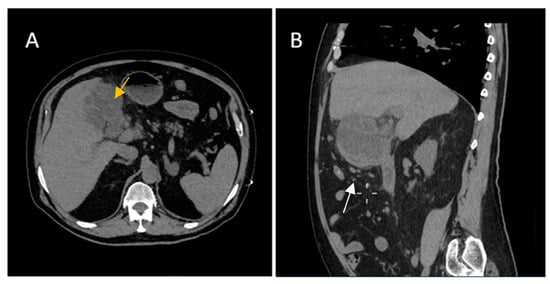

A 55-year-old female patient was admitted to the Emergency Department with right hypochondrium pain and weight loss for 2 weeks, which had worsened over the last two days accompanied by nausea and vomiting. No medical history was noted. Physical examination revealed normal abdominal wall mobility with respiratory movements and a sensitive right hypochondrium. Blood sample demonstrated normal levels of leukocytes and inflammatory markers.

Contrast-enhanced emergency CT (Figure 2) revealed mucosal hyperenhancement of the gallbladder, with irregular, mural thickening (16 mm), a gallstone (15 mm) and pericholecystic fluid and loco-regional inflammatory reactive lymph nodes (Panel A, Panel B and Panel C).

The CT scan depicted an abscess adjacent to the gallbladder with subtle peripheral contrast enhancement, measuring up to 12 mm in size along with inflammatory alterations in the adjacent hepatic parenchyma (Panel D). Inflammatory fat stranding can be observed at the omentum, periduodenum and pericolonic areas, as well as free intraperitoneal fluid.

An acute cholecystitis complicated by pericholecystic abscess was diagnosed. The patient refused hospitalization and specialized treatment. The following day the patient returned to the Emergency Department with severe pain and was admitted directly to the General Surgery Department. Nevertheless, blood sample demonstrated increased levels of CEA (67.83 ng/mL) and CA 19-9 (110.20 U/mL), markers which brought to question the CT imaging diagnosis of an acute cholecystitis complicated by pericholecystic abscess.

Therefore, clinical suspicion of gallbladder carcinoma was raised and an MRI cholangiography was performed (Figure 3). A laparoscopic cholecystectomy was performed and a subhepatic tumoral block with transvers colon invasion was identified. The patient was referred to the Oncology Department for further specialized treatment and follow-up.

Figure 2. Multiplanar sections of contrast-enhanced CT acquisitions richly illustrating gallbladder carcinoma. (A,B) Gallbladder with irregular mural thickening, 16 mm (white arrow), pericholecystic fluid and loco-regional inflammatory lymph nodes. (C) Gallbladder with an intraluminal gallstone, 15 mm (black arrow). (D) Abscess adjacent to the gallbladder with subtle peripheral contrast enhancement (yellow arrow).